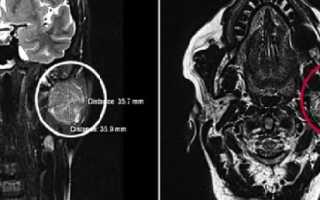

С помощью МРТ слюнной железы врач может обнаружить большое количество самых разных заболеваний, которые невозможно диагностировать иным методом. Таким образом специалисты выявляют опасные патологии, течение которых протекает бессимптомно и незаметно для пациента. Особенно часто магнитно-резонансная томография используется для обнаружения кистовидных изменений и опухолевых образований (вследствие высокой чувствительности прибора сканирование органа происходит очень тонкими срезами сразу в нескольких плоскостях, а потому становятся хорошо видны даже самые незначительные изменения в структуре тканей).

МРТ с контрастированием проводят при подозрении на злокачественное новообразование в слюнных железах (в том числе и при наличии метастаз). Контрастное вещество, проникая в ткани органа, позволяет более отчетливо визуализировать контуры, границы и размеры опухоли, а также оценить степень ее прорастания в окружающие структуры. Чаще всего при этом используются смеси на основе гадолиния (при исследовании выводных протоков применяют обыкновенный физиологический раствор).